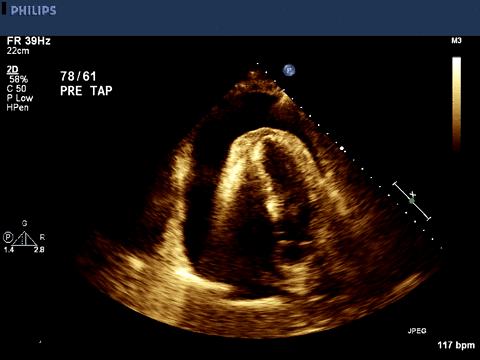

Image 2 shows an apical 4-chamber view, with pericardial effusion and

right atrial collapse. The right atrium is the thin-walled chamber on

the lower left of the image of the heart. The right ventricular wall is

hyperechoic, which obscures some of the distal structures.